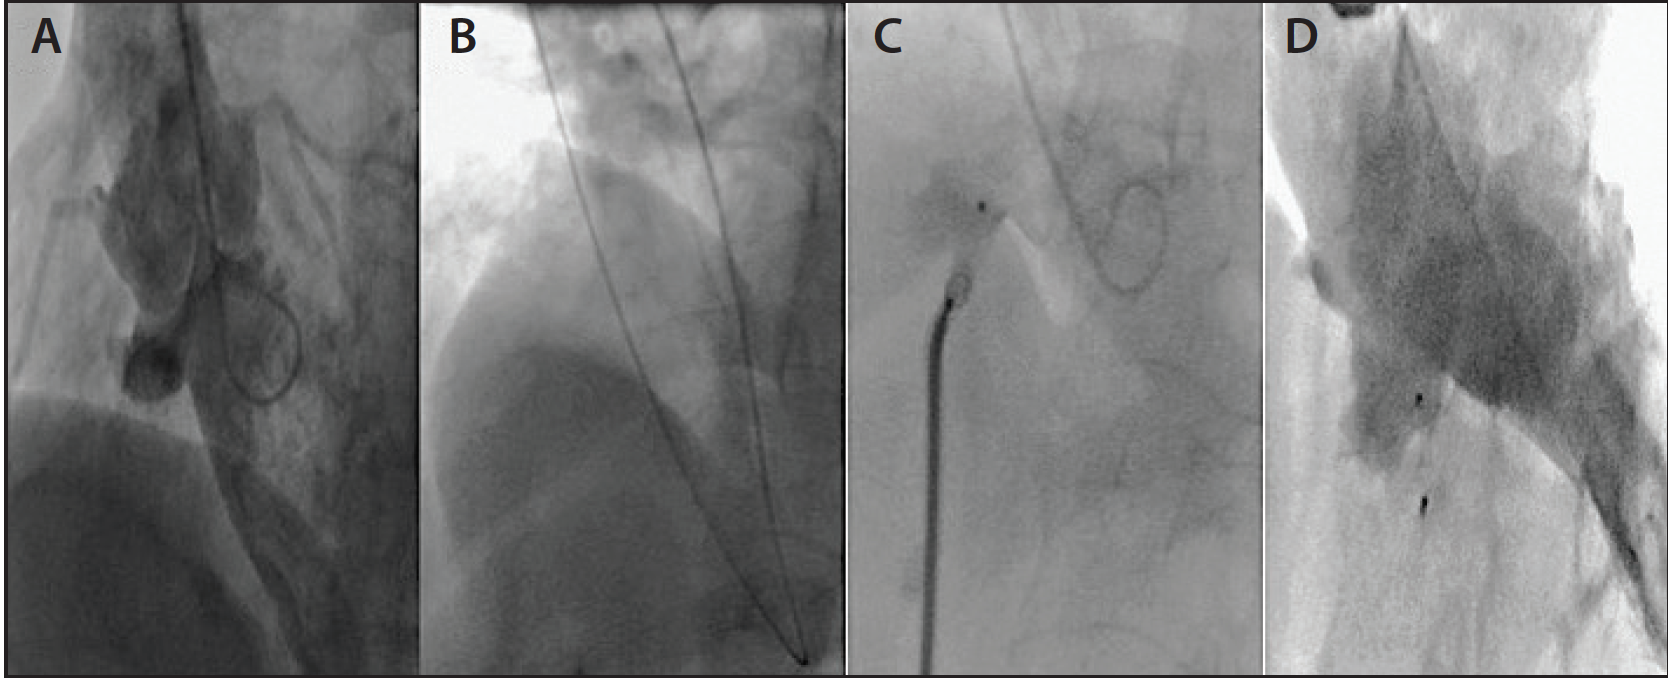

Figure 4. LV angiography showing perimembranous VSD (A). Using a JR 4 catheter from the right RA, a hydrophilic wire was crossed through the VSD into the right ventricle (B). An 8-mm Amplatzer VSD occluder was deployed across the VSD through a 6-F, 90-cm sheath that was advanced from right basilic vein access while a pigtail catheter from the right RA was inserted in the LV for ventriculography (C). Final LV angiography showing the closed VSD (D).

After the early description in 2002, percutaneous techniques and devices have been developed overtly for the closure of perimembranous VSD. Traditionally, femoral artery and vein access or jugular access have been used for VSD closure, but we reported a case of percutaneous closure of a perimembranous VSD through an arm approach (RA and basilic vein) (Figure 4).8 In our experience, crossing a high perimembranous VSD is quite easy from the RA approach using a JR 4 catheter and an angled, torqueable 0.035-inch wire. Although the access-related complications from femoral artery, femoral vein (FV), or internal jugular (IJ) vein access are arguably low, RA and basilic vein access may offer a safer access, or at least provide another alternative, particularly when access choices are limited.

In other instances, we have used a combination of radial artery and FV access or a combination of FA and AVA that can be customized for the anatomy of each individual patient (Figure 5). With the miniaturization of the device profile to a 12-mm diameter, the Amplatzer VSD occluder (St. Jude Medical, Inc.) can be deployed through a 7-F sheath. The basilic vein access is preferred over cephalic vein access. Ultrasound guidance or the levophase technique can be used to determine a fairly large superficial basilic vein.9 As the veins expand, a sheath (> 7 F) can be used through the basilic vein in appropriately selected patients, which will allow the use of a large VSD occluder.

Figure 5. LV angiography showing a complex, very high VSD with an aneurysmal septum (A). The VSD was crossed using a JR 4 catheter via the right RA with an angled hydrophilic wire (B). A VSD occluder was deployed from an FV approach (C). Final angiogram showing the closed VSD (D).